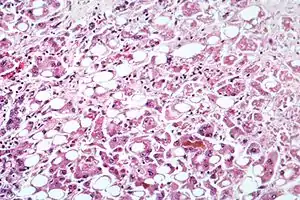

Alcoholic hepatitis as seen with a microscope, showing fatty changes (white circles), remnants of dead liver cells, and Mallory bodies (twisted-rope shaped inclusions within some liver cells). (H&E stain)

Steatohepatitis

Steatohepatitis is seen in both alcoholic and non-alcoholic liver disease and is the culmination of a cascade of events that began with injury. In the case of non-alcoholic steatohepatitis, this cascade is initiated by changes in metabolism associated with obesity, insulin resistance, and lipid dysregulation.[57][58] In alcoholic hepatitis, chronic excess alcohol use is the culprit.[59] Though the inciting event may differ, the progression of events is similar and begins with accumulation of free fatty acids (FFA) and their breakdown products in the liver cells in a process called steatosis.[57][58][59] This initially reversible process overwhelms the hepatocyte's ability to maintain lipid homeostasis leading to a toxic effect as fat molecules accumulate and are broken down in the setting of an oxidative stress response.[57][58][59] Over time, this abnormal lipid deposition triggers the immune system via toll-like receptor 4 (TLR4) resulting in the production of inflammatory cytokines such as TNF that cause liver cell injury and death.[57][58][59] These events mark the transition to steatohepatitis and in the setting of chronic injury, fibrosis eventually develops setting up events that lead to cirrhosis and hepatocellular carcinoma.[57] Microscopically, changes that can be seen include steatosis with large and swollen hepatocytes (ballooning), evidence of cellular injury and cell death (apoptosis, necrosis), evidence of inflammation in particular in zone 3 of the liver, variable degrees of fibrosis and Mallory bodies.[57][60][61]